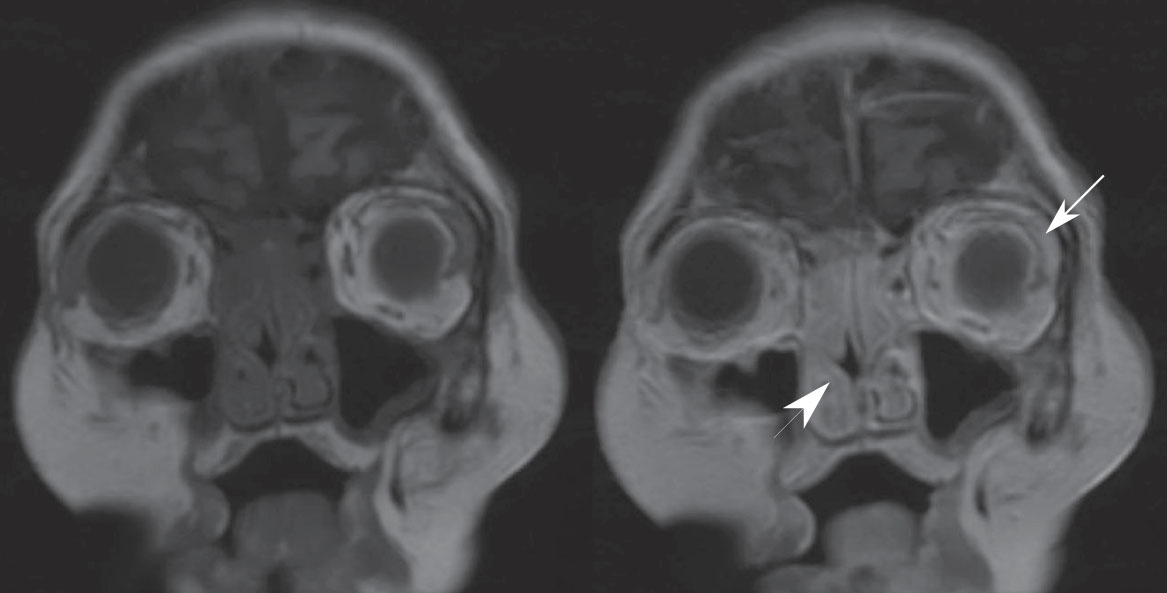

She was transferred to our hospital, at which time she had complete right-sided ptosis and near-complete left-sided ptosis. Her visual acuity was hand-motion-only in the right eye and with the left eye she did not have light perception. She had complete right-sided ophthalmoplegia while her left eye retained a limited ability to abduct. She had bilateral proptosis and conjunctival edema. She had diminished bilateral facial pinprick sensation and a slight right-sided facial droop. Head MRI revealed marked, symmetric paranasal sinus enhancement with periorbital swelling (Figure 1). There were no necrotic areas seen. Her leukocyte count was 42×109/L, hemoglobin was 98 g/L, platelets were 53×109/L, neutrophils were 32×109/L, and monocytes were 8.4×109/L (20% of total leukocytes), with no blasts identified. Her platelet count dropped further, despite a platelet transfusion, so lumbar puncture was not attempted. Given her history of diabetes, steroid use, rapidly progressive cranial neuropathies (II through VII), and proptosis, there was clinical concern for AIFR. She was started on empiric meropenem, vancomycin, and amphotericin B. She underwent nasopharyngoscopic examination, which was unremarkable: her nasal mucosa appeared normal, bled appropriately, and had normal sensation. A middle turbinate biopsy was performed, and histopathological examination of the specimen showed no fungal elements. Despite broad-spectrum antimicrobial therapy, she rapidly developed renal, respiratory, and bone marrow failure and died on her 4th day after admission.

Figure 1 Coronal T1-weighted MRI without (left) and with (right) gadolinium of a 72-year-old diabetic woman with rapidly progressive multiple cranial neuropathies and proptosis. There is symmetric pansinus enhancement (arrowhead) with periorbital tissue swelling and enhancement (arrow). The extraocular muscles appear normal. The cavernous sinuses and pachymeninges enhance symmetrically, although there is no leptomeningeal enhancement (not pictured). No areas of necrosis are seen.